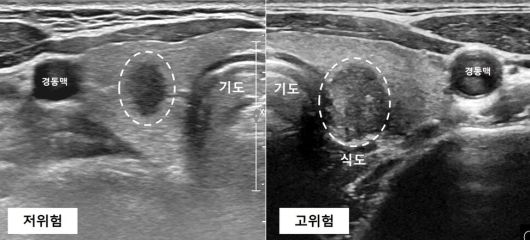

고위험과 저위험 ‘미세(갑상샘)유두암’. 서울대병원 제공 |

미세(갑상샘)유두암은 영상 검사와 임상 소견에 따라 고위험과 저위험으로 구분된다. 고위험 미세유두암은 △목 근처 림프샘 전이 및 원격 전이 △뚜렷한 외부 조직 침범(근육·기관·되돌이후두신경 등) △세포학적으로 예후가 나쁜 아형 등이 관찰된다. 이런 소견이 없는 저위험 미세유두암은 여러 장기 추적 관찰 연구에서 암의 크기가 커지거나 전이되지 않는 경우가 많다고 보고됐다.